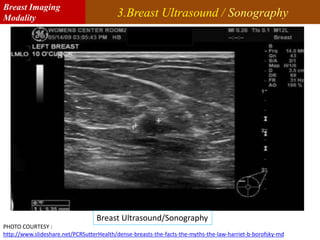

3.Breast Ultrasound / Sonography

PHOTO COURTESY :

http://www.slideshare.net/PCRSutterHealth/dense-breasts-the-facts-the-myths-the-law-harriet-b-borofsky-md

Breast Ultrasound/Sonography